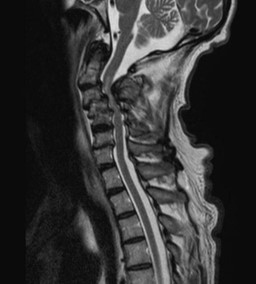

Because of the COVID19 pandemic you are practicing telemedicine. Your patient is a 75-year-old man previously in good health who presents with progressive weakness in his hands and arms coupled with stiffness in his legs. You are told that his neurologic exam was positive for lower motor neuron findings in his upper extremities (weakness, hyporeflexia, some atrophy) and upper motor neuron findings (spaticity, hyperreflexia) in his lower extremities. You are provided an MRI of his spinal cord and a video showing a bedside test.

DIAGNOSIS: Cervical myelopathy secondary to compression of the spinal cord by C2-C5 vetebrae.